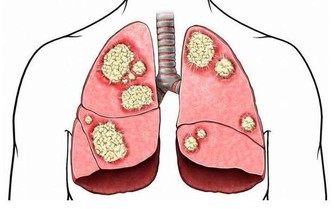

1、會加快前列腺癌的生長速度,會引發腎衰竭脂類的腎臟疾病。

2、會減少人的壽命,尤其是男性的壽命同時和血管有關的中風機率會隨著增加。

3、會阻塞心臟動脈和使其變窄,更容易引發心髒病。